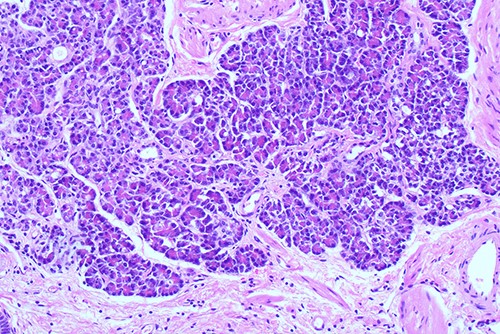

Histological examination ×100 showing ectopic tissue consisting of pancreatic acini and small ducts. No islets are seen.